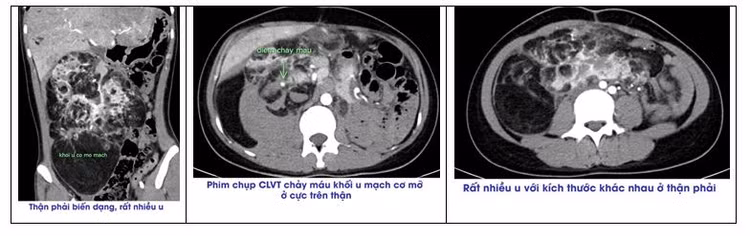

Người bệnh đến khám tại Bệnh viện đa khoa tỉnh Phú Thọ trong tình trạng đau bụng bên phải. Qua thăm khám, chụp cắt lớp vi tính phát hiện rất nhiều khối u mạch cơ mỡ ở thận phải, các khối u kích thước từ nhỏ vài mm đến rất lớn hàng chục cm và có chảy máu từ khối u ở cực trên thận.

Hình ảnh phim chụp cho thấy rất nhiều khối u với kích thước khác nhau ở quả thận phải |

Hình ảnh phim chụp cho thấy rất nhiều khối u với kích thước khác nhau ở quả thận phải